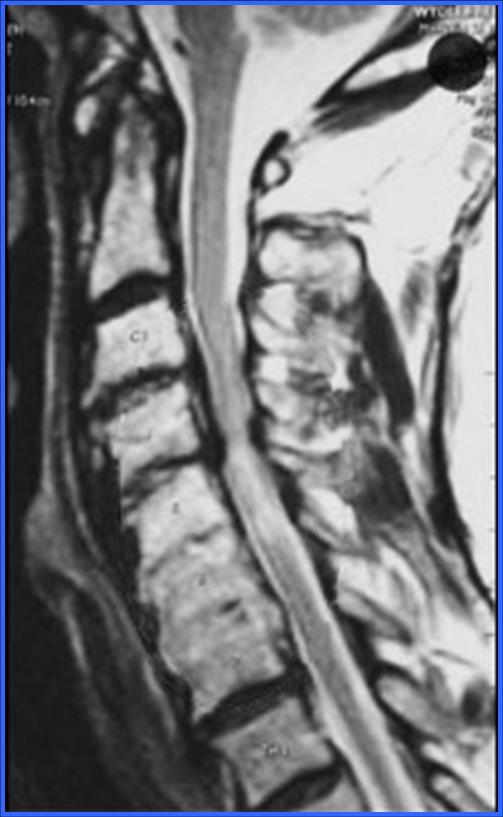

CONDUCTO CERVICAL ESTRECHO (ESTENORAQUIS)

El conducto estrecho comprime la medula espinal y se puede desarrollar una mielopatía, lo que involucra síntomas como alteraciones de la marcha, perdida del equilibrio, adormecimiento de las extremidades y perdida de la coordinación. El tratamiento de ésta patología es quirúrgico y se debe hacer una descompresión para ensanchar el conducto.